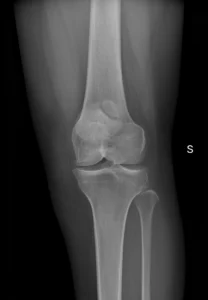

Consulta por dolor anterior de la rodilla. Sin antecedentes de trauma.

Las radiografias ap y oblicuas muestran Se identifica un fragmento óseo accesorio adyacente a la rótula, típicamente en el cuadrante superolateral, con bordes lisos y corticalizados, compatible con rótula bipartita (fallo de fusión de un centro de osificación).

El valor de este caso es evitar un error muy frecuente: confundir rótula bipartita con fractura.

Pistas a favor de rótula bipartita:

Ubicación típica superolateral (la más frecuente).

Bordes redondeados y corticalizados (no “filosos” como en fractura aguda).

Ausencia de signos claros de trauma agudo en partes blandas (según contexto).

A veces es bilateral (si tienes el otro lado, puede ayudar).

La mayoría son asintomáticas, pero puede volverse sintomática (dolor anterior) sobre todo tras actividad o trauma; en ese caso, la RM puede mostrar edema de médula ósea cerca del fragmento, lo que apoya correlación clínica.